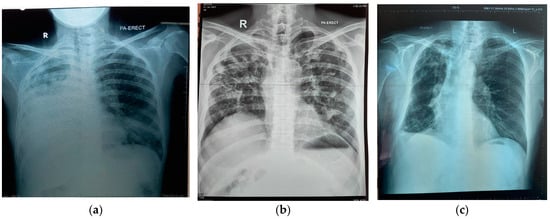

| Lesion area on the chest X-ray | Minimally advanced | 1 | 14 | 4 | 11 |

| Moderately advanced | 5 | 11 | 4 | 12 | |

| Far advanced | 8 | 11 | 8 | 11 |

| Chest X-ray | 4.545 | 0.028 | 1.180 | 17.514 |

| Chest X-ray | Histoplasma Antibody + | Aspergillus Antibody + | Both Antibody + | |||

| Findings | Male | Female | Male | Female | Male | Female |

| Minor changes | 1 | 1 | 2 | 2 | 2 | 2 |

| Moderately advanced | 3 | 2 | 2 | 2 | 2 | |

| Far advanced | 5 | 1 | 5 | 3 | 5 | 3 |